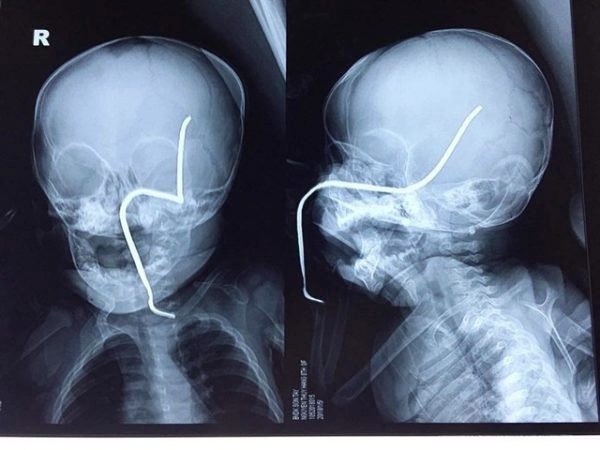

| Hình ảnh phim X-quang của cháu H. |

Theo ThS.BS Hồ Trung Luân, khoa Ngoại Thần kinh - người trực tiếp phẫu thuật cho bệnh nhi, ca mổ khá khó khăn do thanh sắt đâm vào gò má trái qua tổ chức phần mềm của má, đâm thủng sàn sọ, xuyên qua vùng não thái dương và vùng đỉnh sát các mạch máu lớn.

“Thanh sắt cũ, giòn nên rất dễ gãy, lại nằm sát các mạch máu nên nguy cơ chảy máu trong mổ là rất lớn, đồng thời nguy cơ nhiễm trùng não, áp-xe não cũng rất cao” – BS. Luân cho hay.